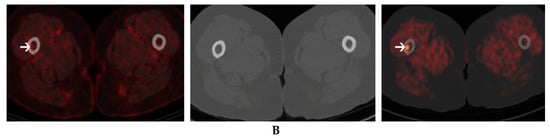

- Nanni, C.; Zamagni, E.; Cavo, M.; Rubello, D.; Tacchetti, P.; Pettinato, C.; Farsad, M.; Castellucci, P.; Ambrosini, V.; Montini, G.C.; et al. 11C-choline vs. 18F-FDG PET/CT in assessing bone involvement in patients with multiple myeloma. World J. Surg. Oncol. 2007, 5, 68. [Google Scholar] [CrossRef] [PubMed]

| Nanni et al. (2007) [25] | 10 | Retrospective | Relapse or f/up post treatment | 11C-Choline 18F-FDG | 5.3 MBq/kg | 5 min. | None | 37 (21/16) | 22 (21/1) | 3 (2/1) | 1 (1/0) | 5.0 (NS) | 3.8 (NS) |